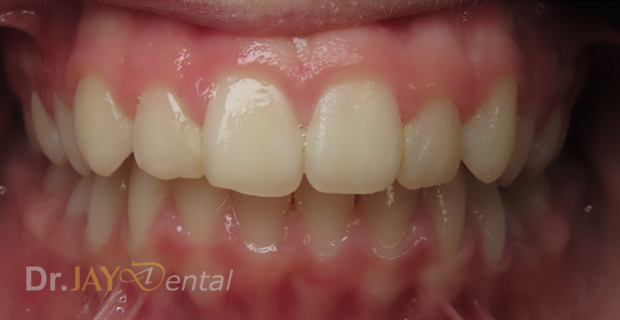

Severe crowding , parent had gone for a consult with 4 Orthodontist to resolve crowding. Orthodontist recommended extraction of multiple teeth to resolve crowding and straighten teeth. At Dr.Jay Dental , Dr. Jay finished the case with no extractions of teeth and just expansion of upper and lower jaws to accommodate all teeth.

Before

After